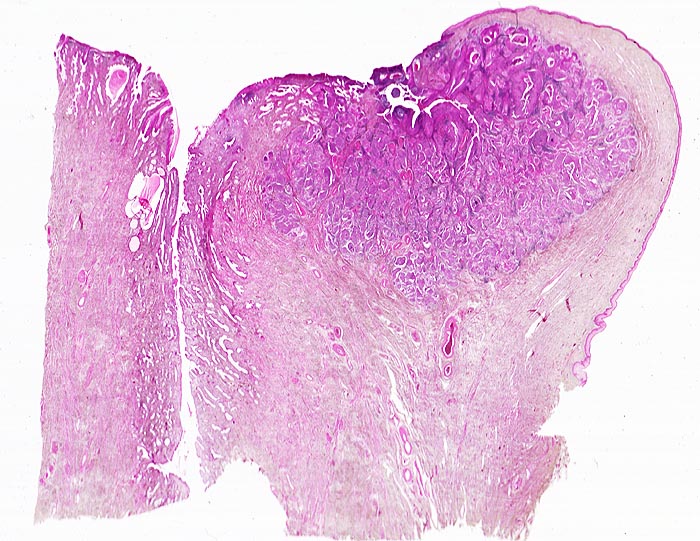

Plattenepithelkarzinom der Zervix

Die Tumorzellen liegen einzeln oder in kleinen Verbänden und ganzen Gewebsfragmenten. Die polymorphen Kerne sind vergrössert und enthalten verklumptes unregelmässig verteiltes Chromatin und grosse Nukleolen. Gut differenzierte Karzinome erkennt man am breiten und oft verhornten Zytoplasma. Längliche bis fadenförmige Tumorzellen mit pyknotischen Kernen können als einziger Hinweis auf das Vorliegen eines Karzinoms vorhanden sein. Wenig differenzierte Karzinome haben polymorphe und schlechter erhaltene Kerne. Der Hintergrund ist meist detritisch und oft hämorrhagisch. Ulzeration, Einblutungen und bakterielle Infektionen beeinflussen den Erhaltungszustand und die Art der abgestrichenen Zellen. Ist die Oberfläche eines ulzerierten Karzinoms von einem Fibrinschorf bedeckt, enthalten die Ausstriche lediglich Detritus, Granulozyten und Erythrozyten, aber keine Tumorzellen. Die Sensitivität für die Karzinomdiagnose ist aus diesem Grund geringer als für die Diagnose eines Carcinoma in situ.